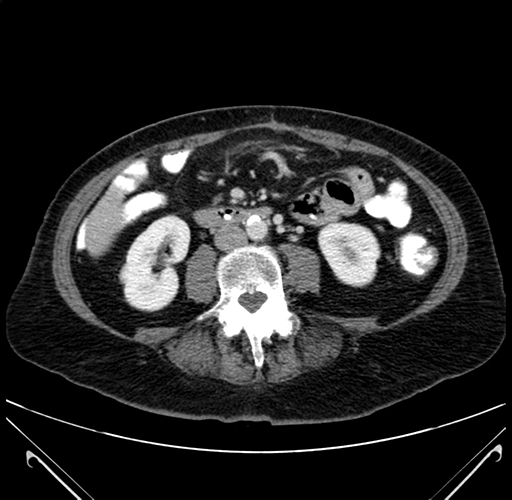

Pre-Chemo: Axial Venous

Axial Venous